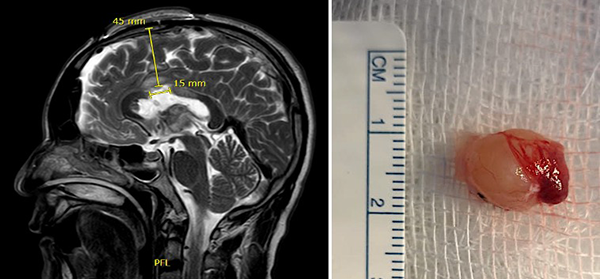

Figura 2. (A) IRM T2W sagital postoperatoria muestra la ruta de aproximación y longitud de la callosotomía; (B) Imagen de pieza quirúrgica mostrando su exéresis total.

Paciente masculino de 40 años, sin antecedentes patológicos, atendido en nuestra institución por presentar cuadro de 2 años de evolución caracterizado por cefalea holocraneana de moderada intensidad, intermitente. Dos meses previo a la consulta inicial había presentado pérdida de consciencia más un episodio de crisis convulsiva tónico-clónico generalizada. Al examen físico el paciente no presentaba deterioro del sensorio ni déficit neurológico evidente. El resto del examen no mostraba hallazgos relevantes. La resonancia magnética (IRM) evidenció una lesión ovoidea que ocupaba el foramen de Monro, isointensa respecto al parénquima cerebral en las secuencias T1 y T2, de 12x9x9 mm, su margen rostral y dorsal en contacto con el pilar anterior y cuerpo del fornix, respectivamente; con tenue realce a la administración del contraste. En la secuencia de tensor de difusión los diferentes tractos se aprecian con trayecto normal y adecuada disposición de las fibras. Sistema ventricular sin dilatación ni compresiones. Se realizó la exéresis total de la lesión a través de un abordaje interhemisférico transcalloso anterior guiado por sistema de neuronavegación (Figura 1). El curso postoperatorio transcurrió con una hemiparesia braquio-crural derecha transitoria, que cede en días subsecuentes con recuperación total de la fuerza muscular. El paciente fue dado de alta sin déficit neurológico agregado. El examen patológico reportó un quiste coloide. La IRM postoperatoria confirmó la extirpación total de la lesión con cambios postquirúrgicos asociados a craneotomía fronto-parietal derecha (Figura 2). El paciente se encuentra asintomático en seguimiento por la consulta externa.